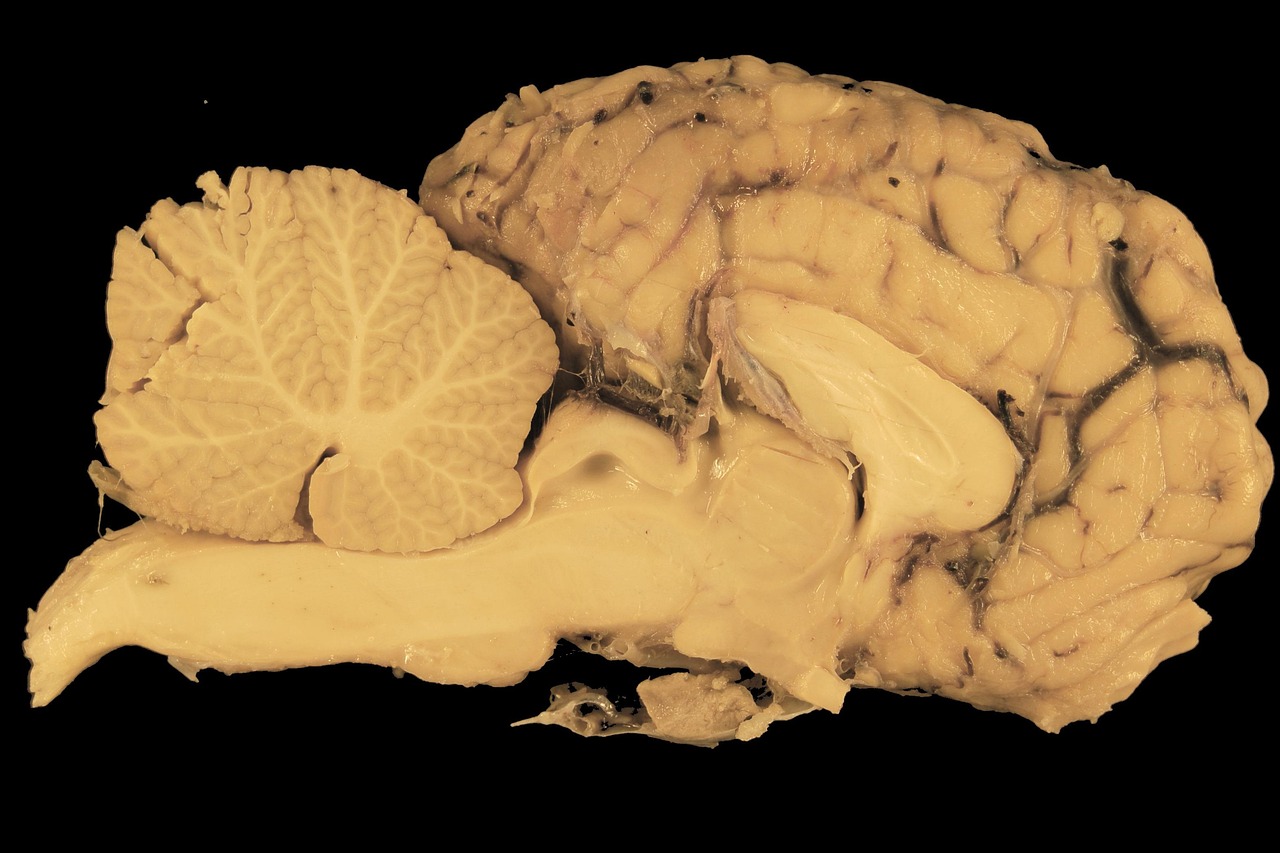

우리나라에서 흔히 발생하는 뇌혈관 질환 중 하나가 바로 뇌경색입니다. 뇌경색은 뇌혈관이 막히면서 혈액 공급이 원활하지 않아 뇌세포가 손상되는 질환인데요. 중요한 점은 뇌경색 초기증상을 빨리 발견하느냐에 따라 후유증과 생존율이 크게 달라진다는 것입니다. 오늘은 많은 분들이 궁금해하는 뇌경색 초기증상과 대처 방법에 대해 자세히 알아보겠습니다. 지금 알려드리는 대처법은 혼자 알고 있어도 되지만 주변 가족분들이 알고 있으면 더 좋겠죠?

뇌경색은 발병 직후 몇 시간 내에 치료를 시작해야 뇌 손상을 최소화할 수 있습니다. 뇌경색 초기증상을 놓치면 치료 골든타임을 놓쳐 반신마비, 언어장애, 기억력 저하와 같은 심각한 후유증이 남을 수 있습니다. 따라서 작은 변화라도 놓치지 않고 즉시 병원을 찾는 것이 생명을 지키는 길입니다.